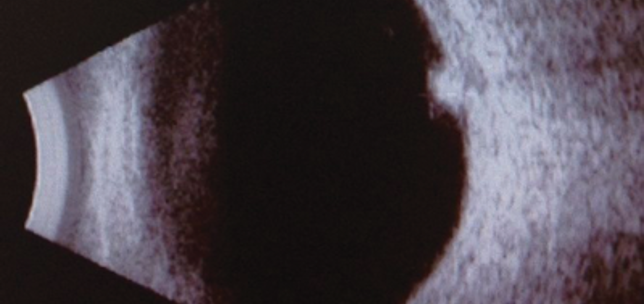

Birdshot chorioretinopathy: an important differential

Zaria Ali

Mohammed Alarbi

Salwa Abugreen

1st April 2015